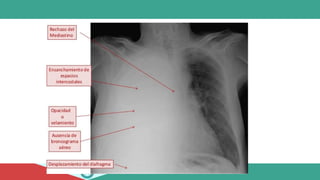

ABORDAJE

• IMAGENOLOGIA:

• SIGNOS PATOGNOMÓNICOS

1. Disminución expansión torácica

2. Disminución murmullo vesicular

3. Hipoventilación

4. Frémito vocal

5. Matidez percutánea